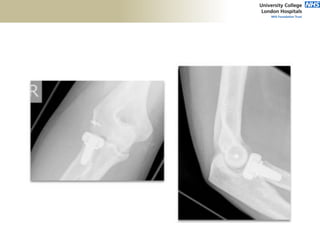

FABS MRI